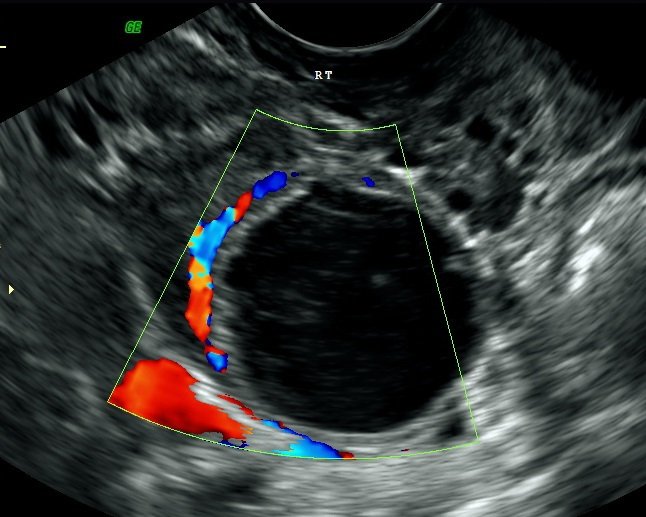

FOLLICLE TRACKING

Day 2-3 – to check for antral follicles, also to exclude any cysts from previous cycle.

Day 9 – to check all the anatomy to exclude fibroids and endometrial polyps. We can also exclude any pathology from the previous cycle.

We measure the lining of the womb (endometrium) and measure the follicles within the ovary (which contain the eggs).

The third scan is performed depending on the size of the follicles and they are monitored to inform you when an estimation of ovulation is likely to occur, which in turn increases your chances of conceiving. When the follicle/s are 20 mm they will rupture – this is ovulation.

A further forth scan can be performed after ovulation, a corpus luteal cyst should be present to ensure ovulation has occurred; this will give you an insight of how the ovaries are working within it and whether you are definitely ovulating.